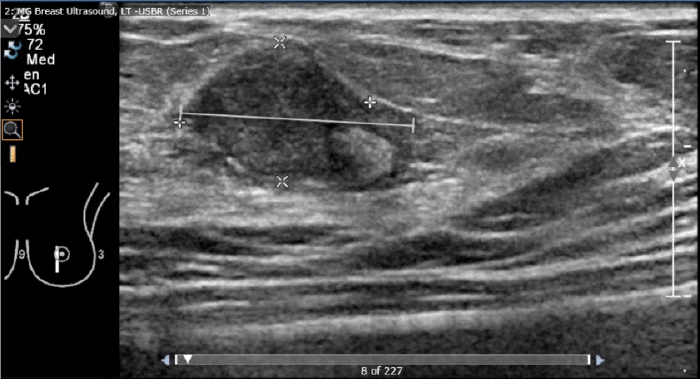

During HT workup, a mammogram identified a nodule less than 2 cm in size (Figure 1). Ultrasound examination supported the diagnosis of a fibroadenoma (Figure 2). Based on these findings, the patient opted for conservative management with regular mammographic follow-up rather than surgical intervention. Her HT regimen with estradiol and spironolactone was continued.

Figure 2. Breast Ultrasound Demonstrating 16 mm Abnormal Intramammary Lymph Node with Features Suggestive of Benign Etiology. Published with Permission